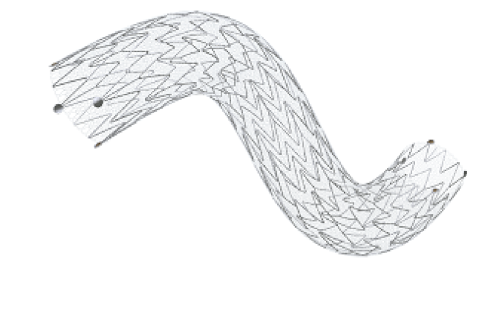

Na área de Cardiologia Intervencionista, fornecemos dispositivos de ponta, como stents, cateteres e balões, que são essenciais para a realização de angioplastias e outros procedimentos cardíacos minimamente invasivos. Nossos produtos são projetados para oferecer máxima eficiência e segurança, contribuindo para a rápida recuperação dos pacientes e a redução de complicações pós-operatórias.

Em Cirurgia Vascular, Endovascular e Radiologia Intervencionista oferecemos uma ampla gama de soluções, incluindo enxertos endovasculares, cateteres de trombectomia e dispositivos de embolização. Esses produtos são vitais para o tratamento de doenças vasculares complexas, como aneurismas e tromboses, proporcionando aos profissionais de saúde as ferramentas necessárias para intervenções precisas e eficazes.

Nossa atuação em Neurorradiologia Intervencionista inclui a oferta de microcateteres e stents especializados para o tratamento de aneurismas cerebrais e outras condições neurológicas críticas. Esses dispositivos são desenvolvidos com tecnologia de ponta para garantir a máxima segurança e eficácia durante os procedimentos, ajudando a preservar a integridade cerebral dos pacientes.